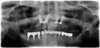

3 implants cylindriques en bas à gauche, parallèles entre eux, et parallèles à l’axe des dents voisines, avec leurs piliers et couronnes, remplaçant les racines des 2 premières molaires

3 implants cylindriques en bas à droite, parallèles entre eux, et parallèles à l’axe des dents voisines, avec leurs piliers et couronnes, remplaçant les racines des 2 premières molaires